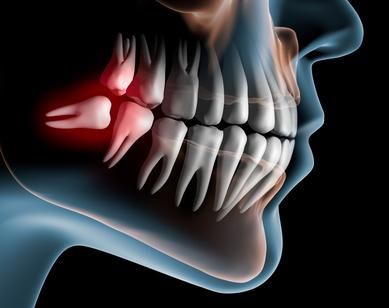

Cirugía bucal

La cirugía oral o bucal tiene la finalidad de solucionar patologías dentales severas. Además, permite corregir aquellos problemas referentes a la salud bucodental del paciente, como la gingivitis o la extracción de piezas dentarias.